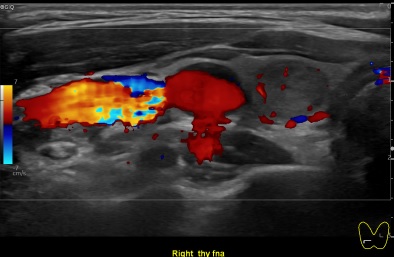

상기환자 목에 이물감 느껴져 검사위해 내원하신 40대초반 여성분으로

의심스러운 갑상선 우엽 결절 세포검사 진행후 갑상선암으로 진단되었습니다